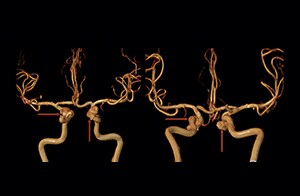

“The 3D TOF MR angiograms are obtained by using 3D T1- weighted FFE sequences (TR 35 ms, TE 7 ms, flip angle 20 degrees, field of view 250 × 190 × 108 mm, matrix 732 × 1024, four slabs, 180 slices of 0.8 mm thickness, acquisition time 8:56 minutes). On our Achieva 3.0T MRI system with an 8-channel head coil, 3D TOF is easy to use and the background signal suppression is very good. Maximum intensity projections (MIPs) and volume-rendered images are reconstructed from the data. We use a single-artery highlighting method to reduce arterial overlay. The method can also be used for carotids or other small intracranial vessels.”

“Advances in MR imaging, the high SNR and spatial resolution of 3.0T, increasing observer experience and improved postprocessing techniques have improved the capabilities of MRA over the last decade. We found that 3D TOF MRA provides excellent images for the visualization of small cerebral aneurysms which enables us to accurately diagnose, and this accuracy appears to be similar to that obtained with DSA according to data from a 2014 study," [2] Dr. Li says. “Aneurysm location can influence how easy it is recognized. Infundibula can mimic aneurysms, adding to the difficulty of interpretation. On MIP images, small aneurysms can also be easily misinterpreted when the aneurysm overlaps with the vessel. This is why in our method we are viewing the images from multiple angles.” “In the hundreds of patients with aneurysms that we scanned, we saw no significant differences in accuracy, sensitivity or specificity among the locations. [2] We think this is the result of technical advances in image acquisition and postprocessing algorithms.”

“Our high confidence in the 3D TOF MRA method was the reason to select this method for a study on the prevalence of unruptured cerebral aneurysms in Chinese adults, which involved finding the location and size of unruptured cerebral aneurysms. By the way, that study found a prevalence of 7% and most lesions had a diameter of less than 5 mm," [3] says Dr. Li.